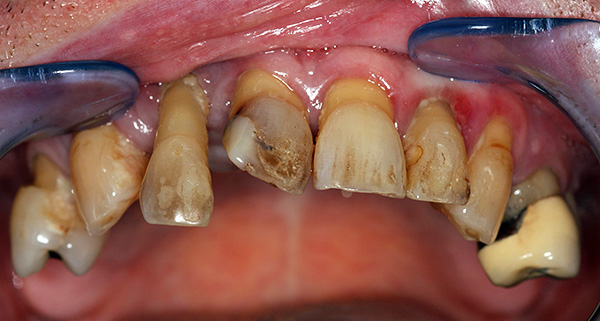

Exemplo 1, antes do tratamento:

Exemplo 2, foto antes do tratamento: